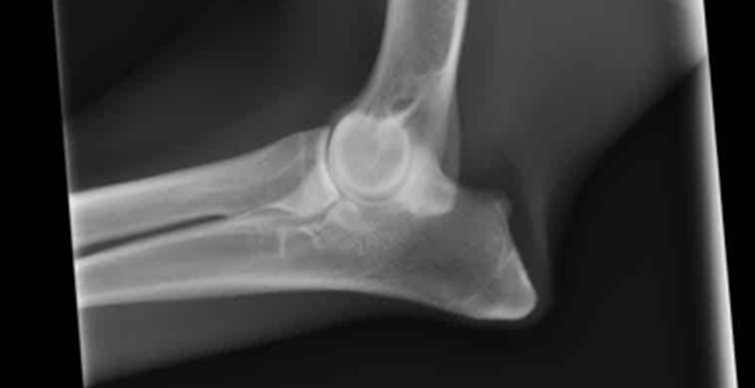

私達がラブラドゥードルの親犬を検討する際に最も重要視していることのひとつが、股関節と肘関節のスコアです。

このスコアにより、ラブラドゥードルの股関節及び肘関節形成不全の可能性を最小限に抑えることができます。

Kiwi Prideでは、スコアが基準値未満の親犬を選び、交配を計画するたびにこれらを考慮に入れることで、遺伝的に受け継がれる可能性を限りなく低くする事に役立てています。